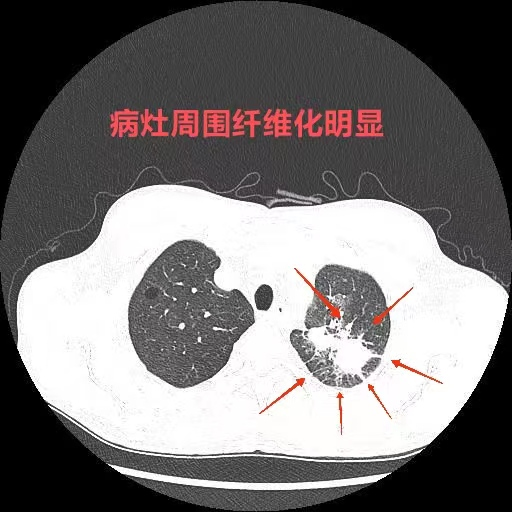

这个间质性肺炎,还挺少见的_肺泡_显示_患者